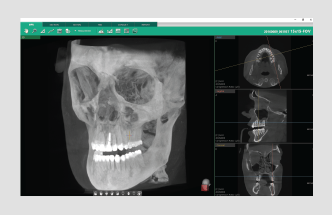

Powered by a new 3D VR graphics engine, the Ez3D-i is the ideal tool to effortlessly obtain the correct perspectives needed for accurate and true-to-measurement diagnosis.

• Various VR coloring modes and 2D filters

Quickly and easily switch between multiple VR views